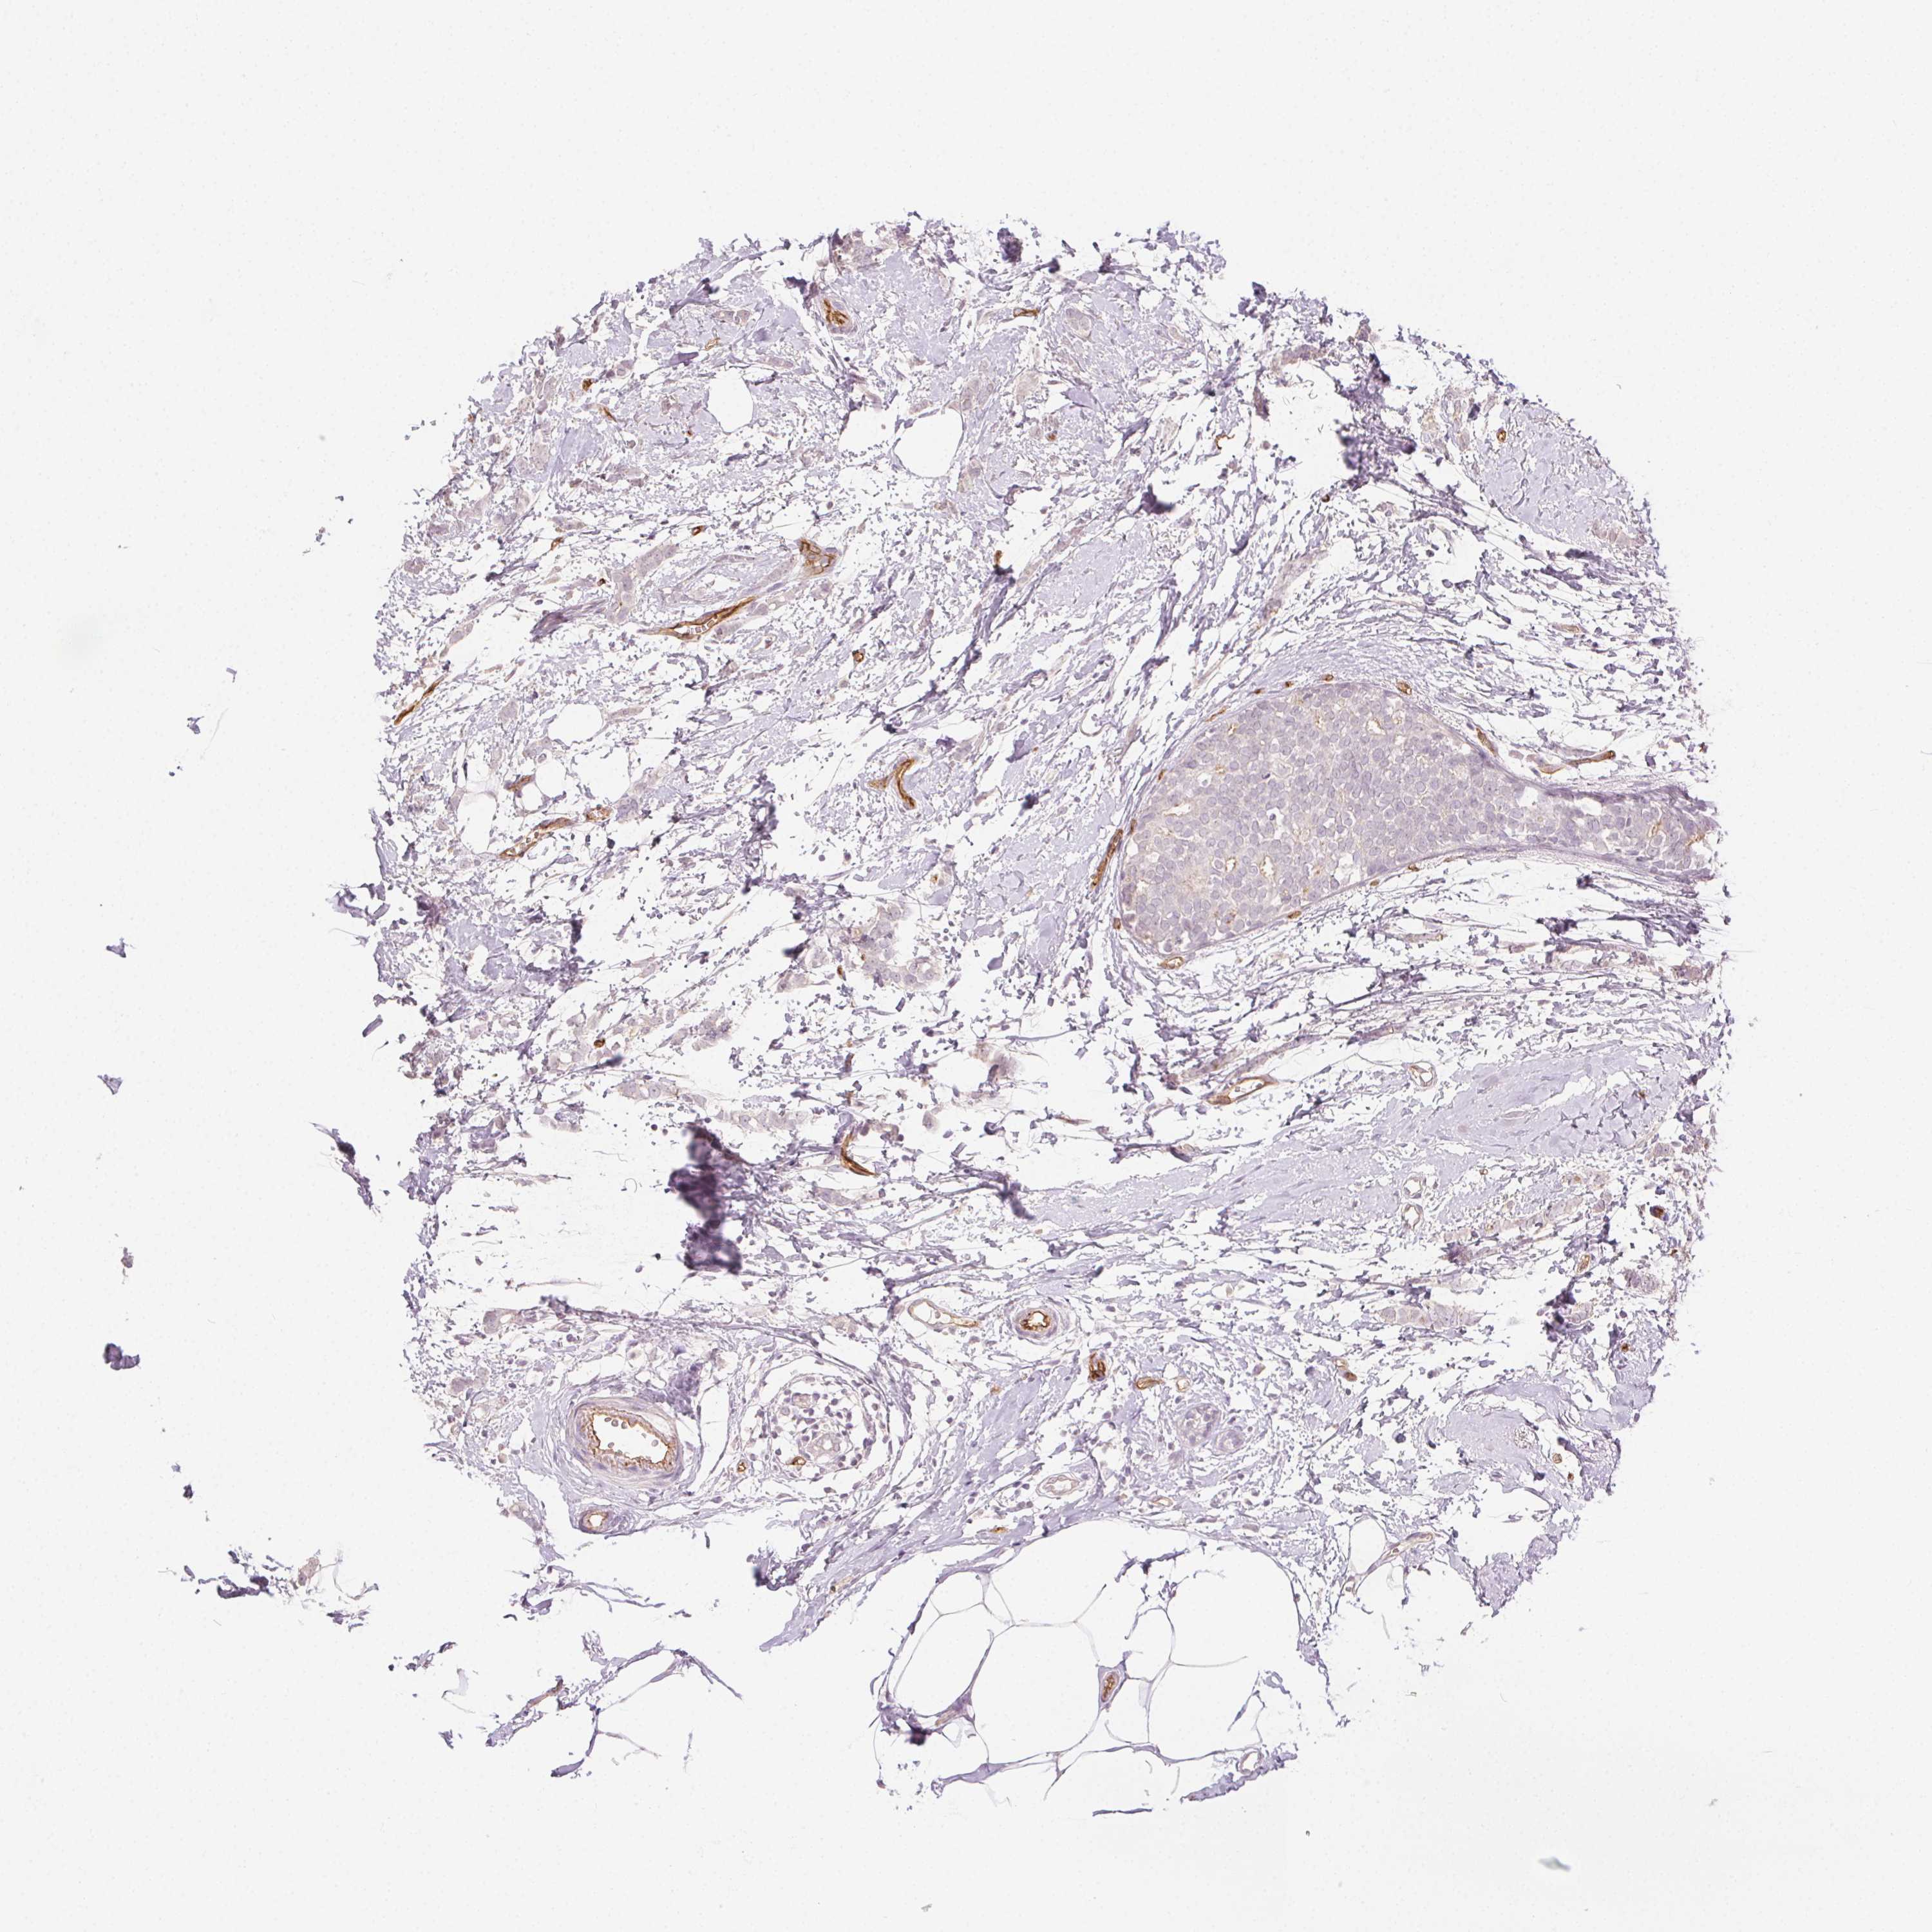

CANCER BREAST CANCER Show tissue menu

BRCA TCGA BRCA VALIDATION PROTEIN EXPRESSION